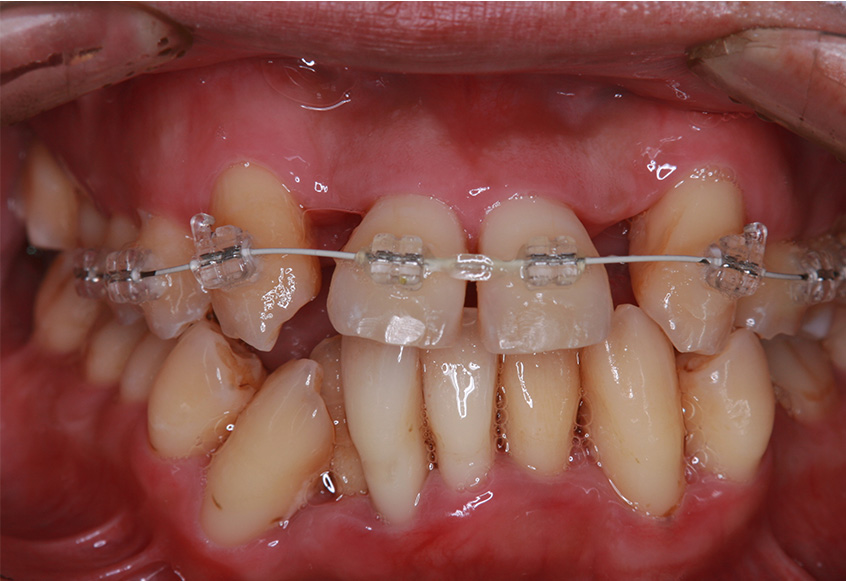

6ヵ月経過すると、矯正治療を終了し、前歯に被せ物の治療を行いました。

最初のお口の中 2025/3/22

被せ物装着

| 治療内容 | 上顎側切歯を2本抜歯した後、上顎の歯にブラケットを装着し、ワイヤー、矯正用ゴムで歯の移動を行いました。その後、被せ物の治療を行って治療を終了しています。 |